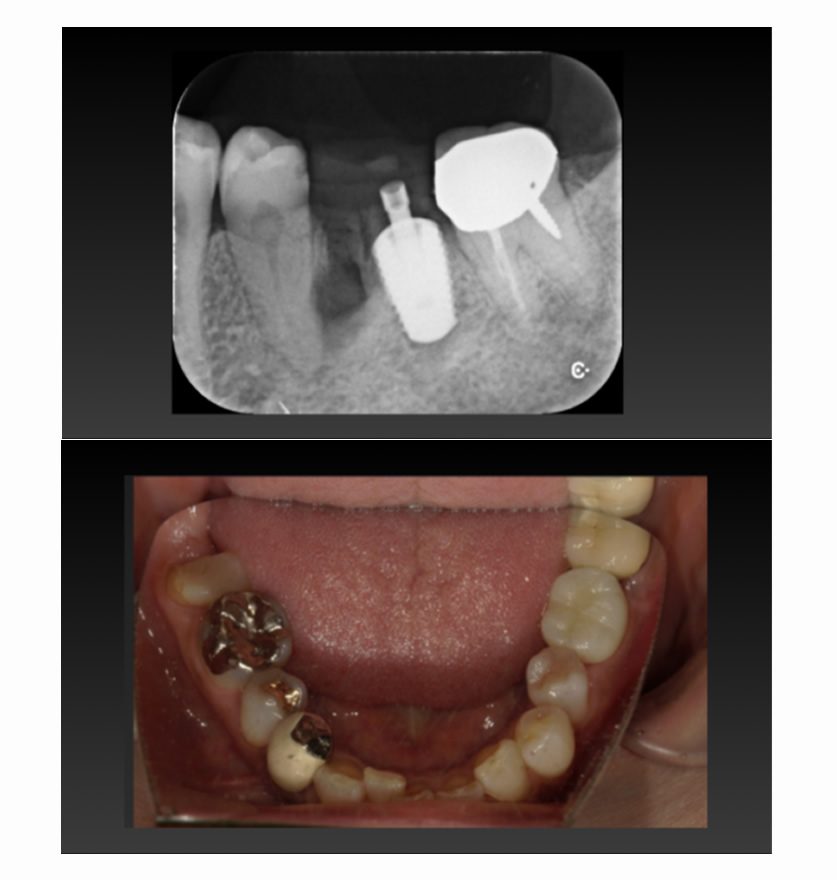

05 症例

歯が割れ、咬むと痛いのでインプラントにしたい

Before

After

| 治療内容 | 歯が割れていて咬むと痛いのでインプラント希望 |

| 患者さま | 60代女性 |

| 主訴 | 咬むと痛いのでインプラントにしたい |

| 治療期間(目安) | 3ヶ月 |

| 治療費(税込:目安) | ¥518,100 |

| リスク | 術後に多少の痛みや腫れが出ることがある。歯肉退縮がおきると、歯と歯肉の間に隙間が生じることがあります。 |